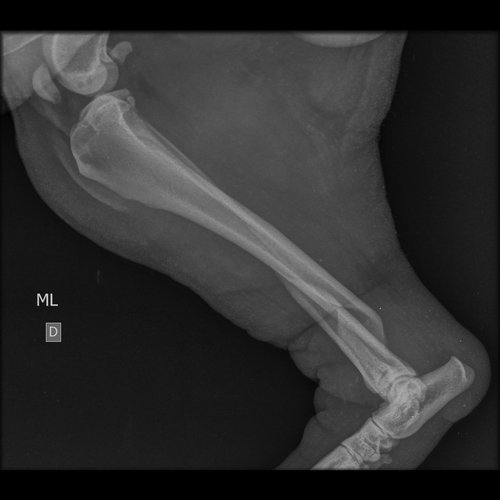

Oi, eu sou a Maria Eduarda, estudante de medicina veterinária e hoje chegou na clínica que eu estou estagiando, um cachorro de rua atropelado, com fratura em femur e tibia e doença do carrapato.

Ele precisa passar por cirurgia e não tenho condições de arcar com os custos.

Os médico veterinários irão fazer a cirurgia e o tratamento dele com o preço de custo, então o valor já foi feito para ajudar o cãozinho. Mesmo assim é um valor que foge um pouco do meu orçamento e como ele é de rua, não tem ninguém parar arcar com tudo.

Nos ajude a salvar o Grandão e dar uma vida digna para ele.